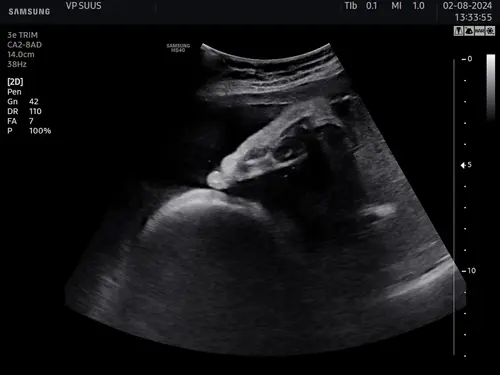

Hier een zoontje met grote voeten. Hadden ze tijdens een groeiecho al gezien en bij ons klopte dat dus. Maar het hoeft natuurlijk niet altijd te kloppen, zo'n echo is maar een schatting . Ik zou me er vooral niet druk om maken. En ook al zou je kindje grote voeten hebben, daar is niks mis mee 😉